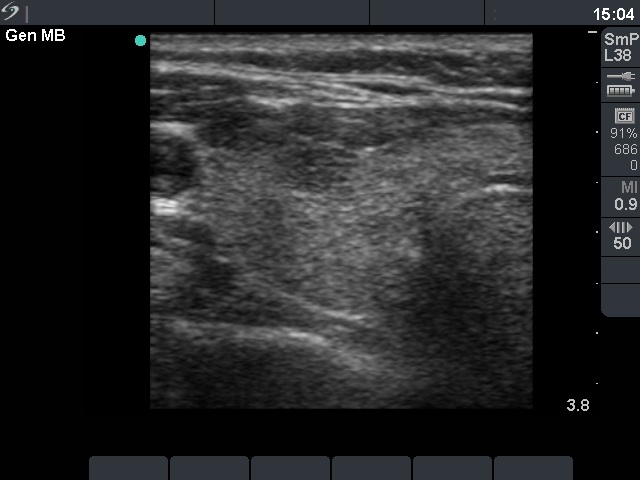

Hashimoto thyroiditis - Case 61

Right lobe, horizontal view

Compare the two series of pictures. Hashimoto's thyroiditis frequently has a similar appearance as observed in the case of de Quervain's thyroiditis. The patchy appearance i.e. hypoechogenic areas within an echonormal background is observed in around 70% of the former, while in more than 90% of the latter disease. In contrast with subacute thyroiditis, the hypoechogenic areas in most of the Hashimoto's cases have irregular but sharp borders. In the cases demonstrated above, the only difference between the ultrasound appearance is the pattern of the hypoechogenic areas. These foci are more blurred in the case of subacute thyroiditis. Nevertheless, the sonographic pattern itself is not diagnostic.